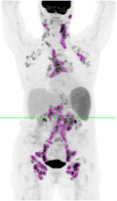

Several of these studies have reported the value of total metabolic tumor volume (TMTV) as a negative or positive prognostic indicator, based on a TMTV above or below a predetermined threshold at baseline, or as an indicator of response according to a change in TMTV over a course of treatment. Different approaches have been investigated for segmenting lesions for volume measurement, including the setting of image thresholds at fixed percentages of lesion maximum standard uptake values (SUVmax), e.g., the 41% of SUVmax suggested by the European Association of Nuclear Medicine (EANM); absolute SUV, e.g. SUV>= 4.0 as advised by the PETRA group; or a multiple of a reference value such as 2.5 times the Liver SUVmean. Although more than one group has concluded that the selection of the most sensitive baseline TMTV cutoff for the purpose of prognostic determination appears to be disease-specific, there is consensus that most, if not all, of the approaches to threshold setting have similar prognostic or response results when the selected method is applied consistently. In addition, at least one group of researchers have reported that FDG-PET-based TMTV evaluations are superior to approaches such as measurements of anatomical size or bulk or qualitative PET assessments such as numerical scoring systems in terms of predicting treatment outcomes or demonstrating response to treatment. TMTV measurements can potentially aid in the selection of patients for appropriate therapies or may support the modification of drug doses for maximum effectiveness.

FDG-PET-based TMTV measurement brings useful, independent, and correlative information to the clinical drug evaluation process. Clario can customize the segmentation threshold settings to meet any special requirements based on disease type or sponsor request or provide measurements based on multiple approaches to segmentation for sponsor downstream evaluation if desired. Additional data, such as Total Lesion Glycolysis (TLG), Fragmentation, and Dissemination based on metabolic tumor volume and distribution of lesions can also be provided for prognostic/response evaluation and can be included in the data provided to the sponsor for a comprehensive demonstration of drug efficacy.